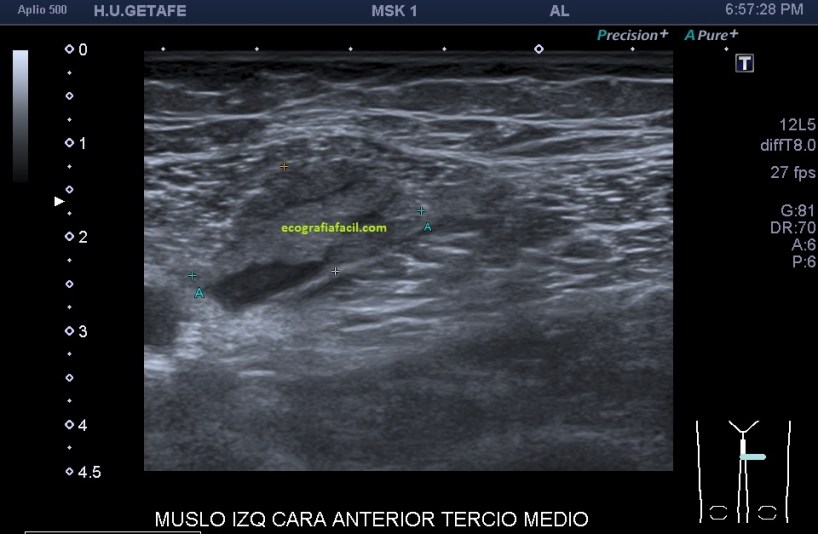

Al explorar la parte interna del muslo, en la zona donde nos señala la paciente encontramos esto…

Una imagen de semiología heterogénea que me pareció una rotura fibrilar importante afectando al interior de un músculo de localización interna del que en un primer momento sospeché que podía ser el vasto interno, pero la anatomía no cuadraba, demasiado interno, demasiado cerca de los vasos…

Después de estudiar la rotura en dos planos (imagen 1 y 2) y medirla (imagen 3 y 4), documentarla bien referenciándola con la anatomía locorregional, incluidos los vasos (imagen 5), decidí seguir el recorrido del músculo partiendo desde la rotura siguiendo las instrucciones que me había comentado la paciente y me dí cuenta que el músculo afectado cruzaba el muslo desde el tercio proximal del muslo, en la cara anterior de la cadera (en su porción más superficial) hasta la cara interna de la pierna…en concreto desde la espina iliaca antero superior y terminando en la inserción de la Pata de Ganso.

En la imagen 1 observamos la rotura en eje corto, mas flechas rojas señalan el músculo dañado, las amarillas la rotura en si. Observamos la anatomía que la rodea y que es referencia siempre.

Medidas en eje corto.